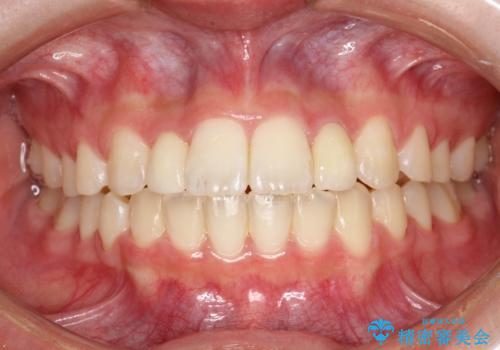

上あごの2番目の歯は矮小歯といって、生まれつき小さい歯となる事がよくあります。

このような場合、矯正によりスペースを集め、本来あるべき形態にセラミックで修正することもできます。

時間はかかりましたが、きれいな笑顔になりました。

かぶせ物の種類:PFZ standard